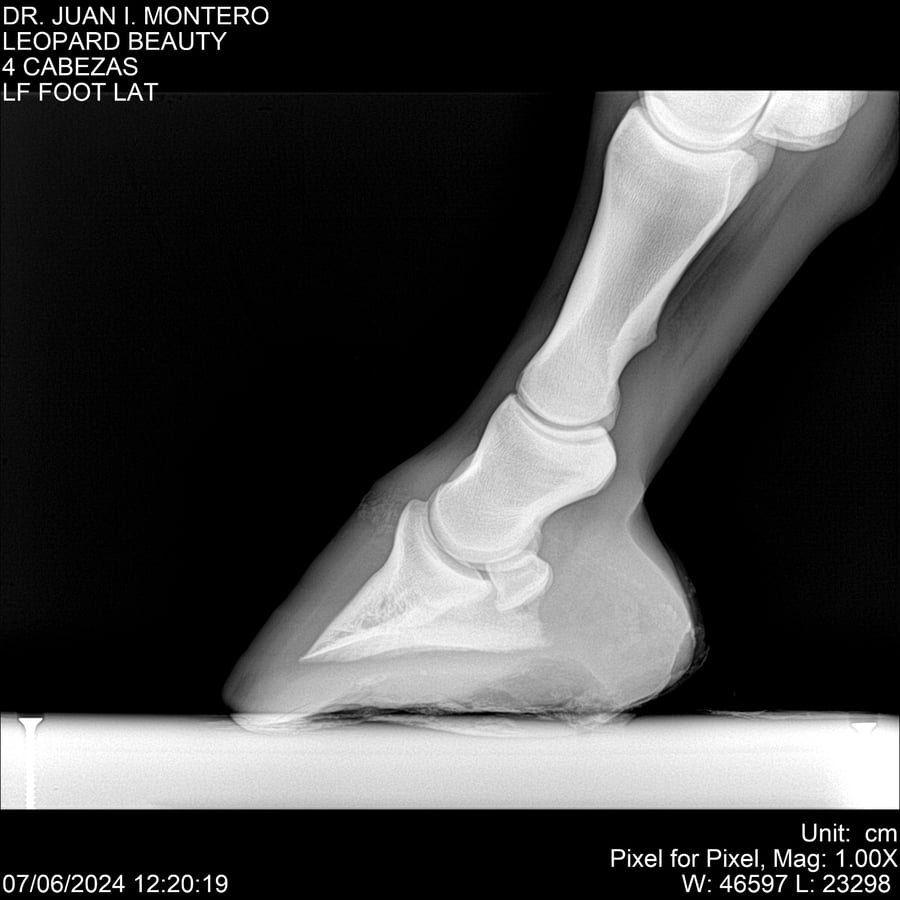

LOTE 16, LEOPARD BEAUTY Lote Anterior Volver al remate Lote Siguiente Ficha Contacto Montevideo - Ficha del Lote Identificador: #281095 Categoría: Yeguarizos Montevideo - 50 Visualizaciones ClicData Contacto Empresa: Abelenda N. R., Walter Hugo Nombre*: Teléfono* : E-mail* : Mensaje Enviar Registrese gratis Este contenido Exclusivo está disponible sólo para usuarios registrados Ingresar